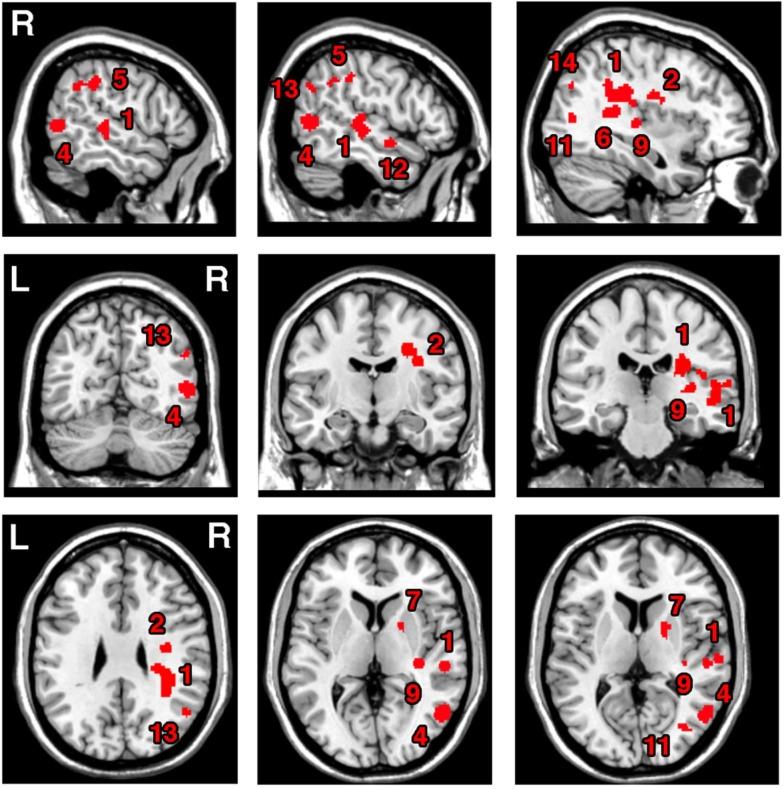

Unilateral visual neglect is commonly defined as impaired ability to attend to stimuli presented on the side of visual space contralateral to the brain lesion. However, behavioral analyses indicate that different neglect symptoms can dissociate. The neuroanatomy of the syndrome has been hotly debated. Some groups have argued that the syndrome is linked to posterior parietal cortex lesions, while others report damage within regions including the superior temporal gyrus, insula, and basal ganglia. Several recent neuroimaging studies provide evidence that heterogeneity in the behavioral symptoms of neglect can be matched by variations in the brain lesions, and that some of the discrepancies across earlier findings might have resulted from the use of different neuropsychological tests and/or varied measures within the same task for diagnosing neglect. In this paper, we review the evidence for dissociations between both the symptoms and the neural substrates of unilateral visual neglect, drawing on ALE (anatomic likelihood estimation) meta-analyses of lesion-symptom mapping studies. Specifically, we examine dissociations between neglect symptoms associated with impaired control of attention across space (in an egocentric frame of reference) and within objects (in an allocentric frame of reference). Results of ALE meta-analyses indicated that, while egocentric symptoms are associated with damage within perisylvian network (pre- and postcentral, supramarginal, and superior temporal gyri) and damage within sub-cortical structures, more posterior lesions including the angular, middle temporal, and middle occipital gyri are associated with allocentric symptoms. Furthermore, there was high concurrence in deficits associated with white matter lesions within long association (superior longitudinal, inferior fronto-occipital, and inferior longitudinal fasciculi) and projection (corona radiata and thalamic radiation) pathways, supporting a disconnection account of the syndrome. Using this evidence we argue that different forms of neglect link to both distinct and common patterns of gray and white matter lesions. The findings are discussed in terms of functional accounts of neglect and theoretical models based on computational studies of both normal and impaired attention functions.

单侧视觉忽视通常被定义为对出现在与脑损伤对侧的视觉空间一侧的刺激进行注意的能力受损。然而,行为分析表明,不同的忽视症状可能会分离。该综合征的神经解剖学一直存在激烈争论。一些研究小组认为该综合征与顶叶后皮质病变有关,而另一些研究则报告病变发生在包括颞上回、脑岛和基底神经节等区域内。最近的几项神经影像学研究提供了证据,表明忽视行为症状的异质性可以与脑损伤的变化相匹配,并且早期研究结果中的一些差异可能是由于使用了不同的神经心理学测试和/或在同一任务中用于诊断忽视的不同测量方法所致。在本文中,我们借鉴病变 - 症状映射研究的ALE(解剖似然估计)元分析,回顾了单侧视觉忽视的症状与神经基质之间分离的证据。具体而言,我们研究了与跨空间(以自我为中心的参照系)和物体内(以异我为中心的参照系)注意力控制受损相关的忽视症状之间的分离。ALE元分析结果表明,虽然以自我为中心的症状与颞周网络(中央前回和中央后回以及缘上回和颞上回)内的损伤以及皮质下结构内的损伤有关,但包括角回、颞中回和枕中回在内的更靠后的病变与以异我为中心的症状有关。此外,与长联合(上纵束、额枕下束和下纵束)和投射(放射冠和丘脑辐射)通路内的白质病变相关的缺陷高度一致,支持了该综合征的失连接解释。利用这些证据,我们认为不同形式的忽视与灰质和白质病变的不同和共同模式相关。本文从忽视的功能解释以及基于正常和受损注意力功能计算研究的理论模型方面对这些发现进行了讨论。